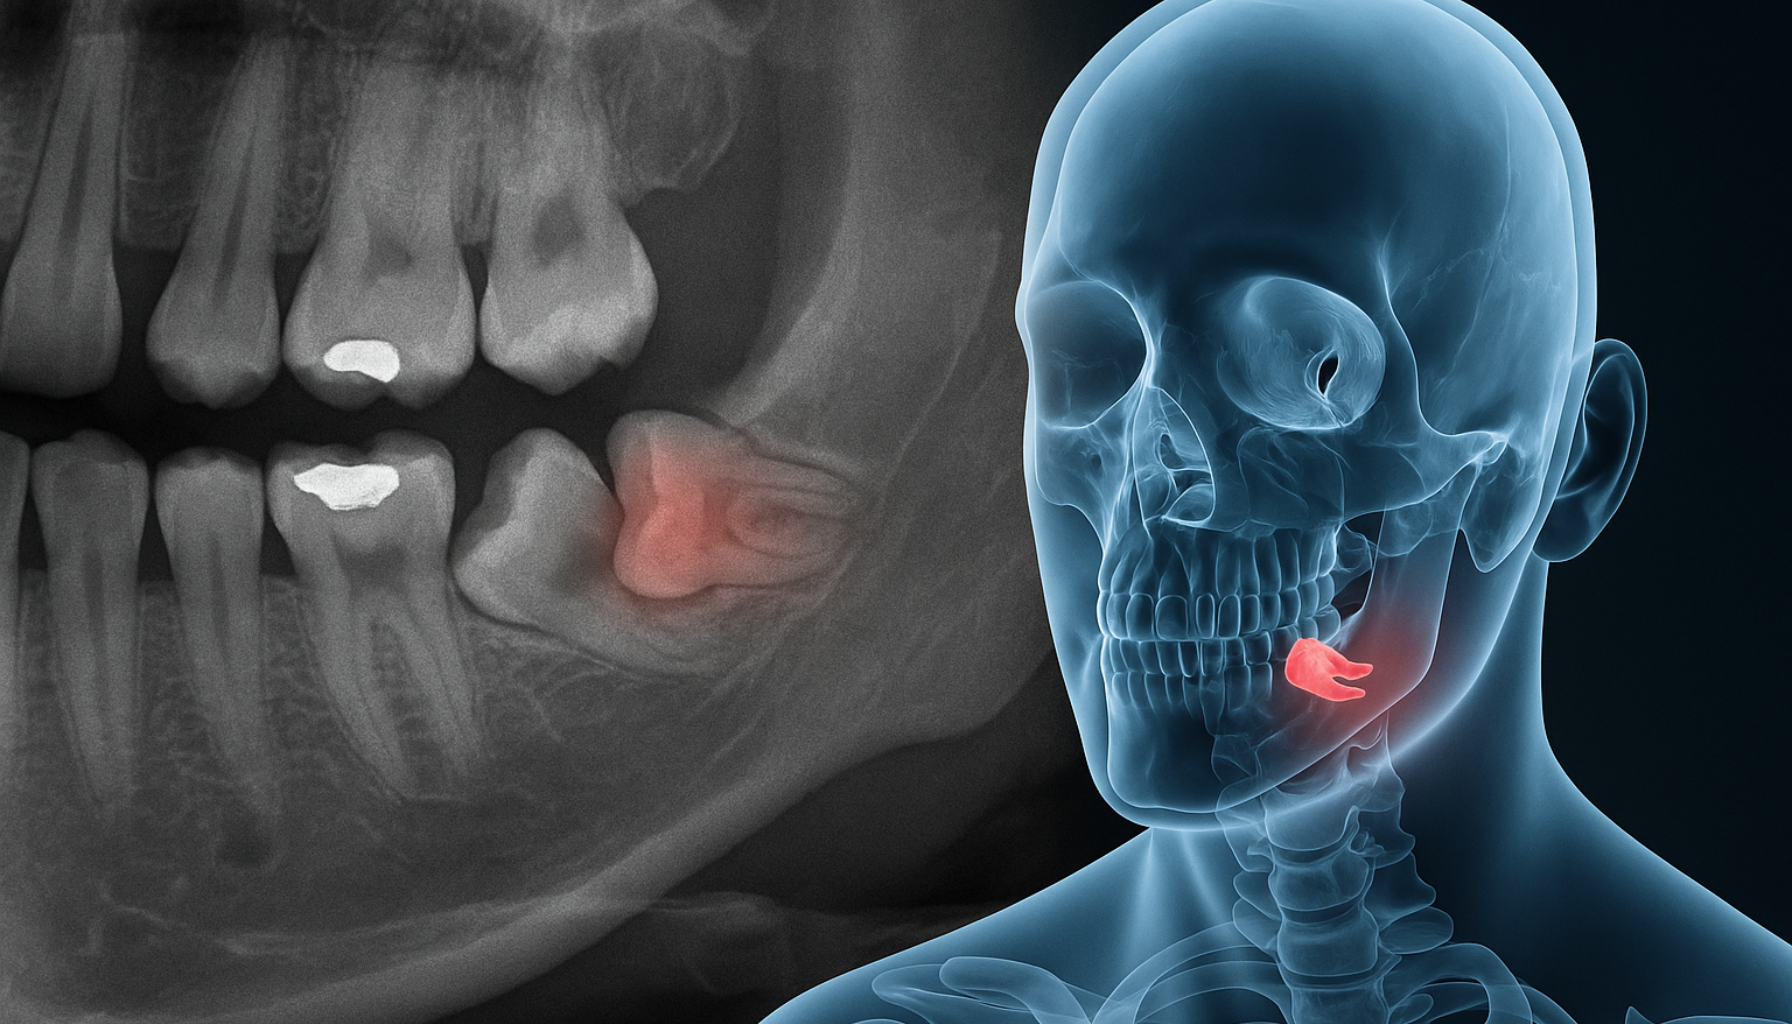

En røntgenundersøkelse hos tannlege avslører om tannen er retinert og hvilken retning den vokser i. Dette gir grunnlag for videre vurdering. Selv om det er en vanlig tilstand, bør den følges nøye opp for å unngå smerter og komplikasjoner.

En røntgen vil vise om det foreligger betennelse eller risiko for skade på nabotenner eller kjevebein. Tidlig oppdagelse og behandling kan forhindre mer alvorlige komplikasjoner. Det er derfor viktig å ta symptomene på alvor, selv om de i starten virker milde eller forbigående.

- Undersøkelse hos tannlegen: Røntgen brukes for å se tannens plassering og vurdere om fjerning er nødvendig.